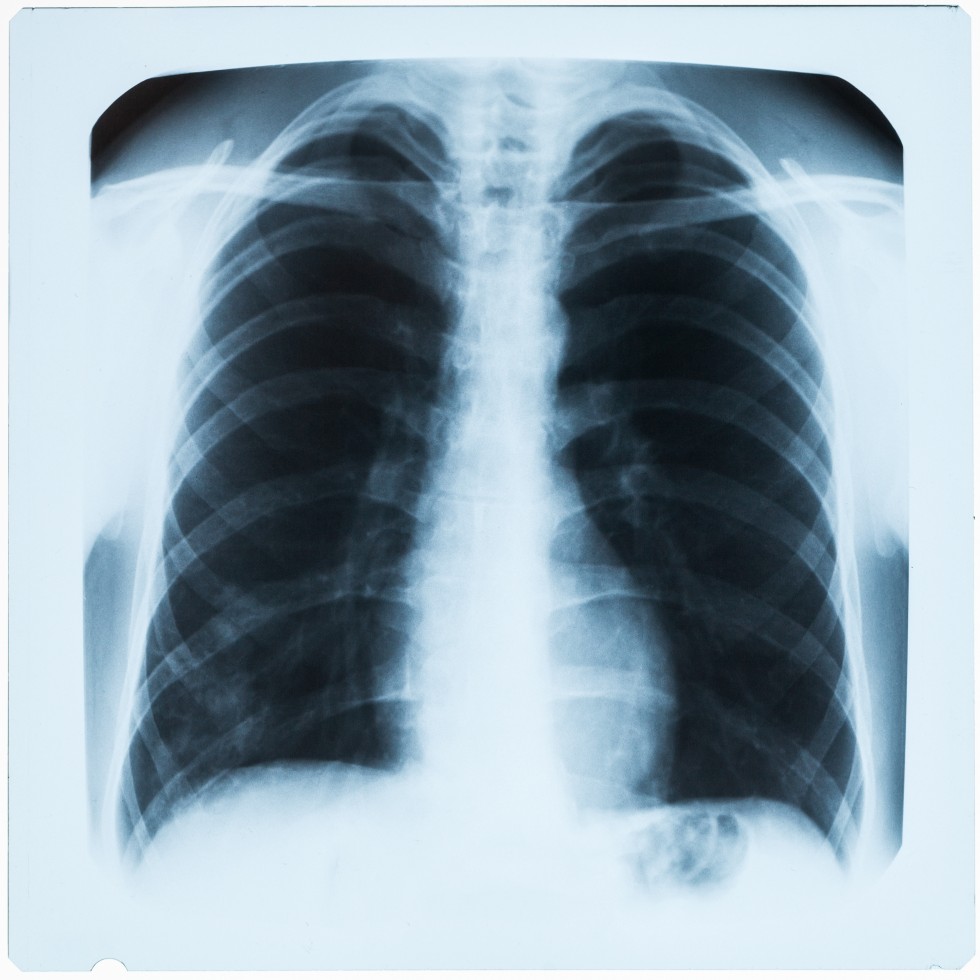

Chest X-ray

Diagnostic radiology is the examination of the tissues and deep structures of the body by X-ray. Fluoroscopy allows the physician to obtain “live” X-ray images and view them on a television screen.